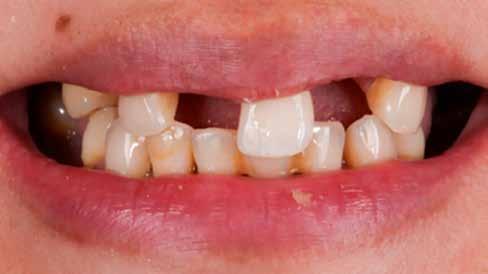

Kiindulási helyzet

A páciens egy 56 éves nőbeteg, nem dohányzik, általános egészségi állapota jó (ASA I), gyógyszert nem szed, ismert allergiája nincs. Fő panasza, amellyel klinikánkat felkereste, hogy elégedetlen mosolyával. Elmondása alapján az utóbbi években krónikus gyulladás alakult ki frontfogai körül, amely érezhető mobilitáshoz vezetett. Ez a probléma jelentősen befolyásolta a magabiztos beszédben és étkezésben. A páciens hosszú távú megoldást keresett, de aggódott a kezelések alatt fellépő esetleges fájdalom miatt. Az extraorális vizsgálat során megállapítottuk, hogy a mosolyvonal közepesen magas és a frontfogak torlódottak (1–2. ábrák). A szájüregi vizsgálat során a 1.2, 2.1 és 2.2 fogak körül előrehaladott parodontális tapadásveszteséget és mobilitást találtunk (3. ábra). A CBCT (cone beam CT) felvételen látszott, hogy a 2.1 fog bukkális csontfala hiányzik (4. ábra).

1. ábra: Az extraorális vizsgálat közepesen magas mosolyvonalat mutatott.

2. ábra: A torlódott felső frontfogak.

3. ábra: Az intraorális vizsgálat során a bal felső nagymetszőnél és mindkét oldali kismetszőnél parodontális tapadásvesztést és mobilitást találtunk.